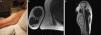

We present a 73-year-old right-handed Jehovah's Witness with a history of mild polio affecting the right arm. MRI showed a slow-growing, cystic mass in the right biceps, originating from the MCN and suggestive of schwannoma. Surgery achieved gross total resection without nerve damage. Histopathology confirmed a cystic schwannoma.

In atypical proximal upper limb tumors, MCN schwannoma should be considered, with US/MRI crucial for diagnosis. IONM-assisted removal can minimize postoperative complications.